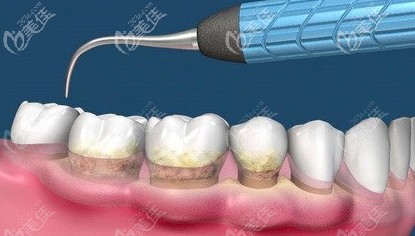

在大部分人的觀念里面,洗牙就是把牙齒表面的臟東西洗干凈,實際上那只是洗牙其中的一部分。其實,洗牙分為齦上潔治和齦下刮治。... b5392 G0 V0

“洗牙”只是一個統(tǒng)稱,在實際的牙科治療中,洗牙分為了4個等級,快來對照看看,你需要的是哪一個級別的洗牙。... b3542 G0 V0